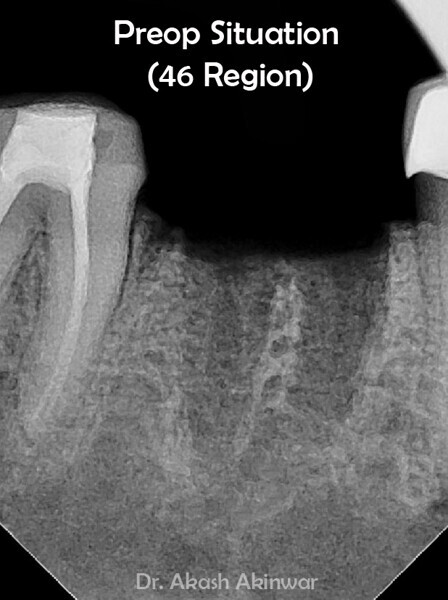

Flapless Single Implant Placement with Screw Retained PFM Prosthesis: Dr Akash Akinwar